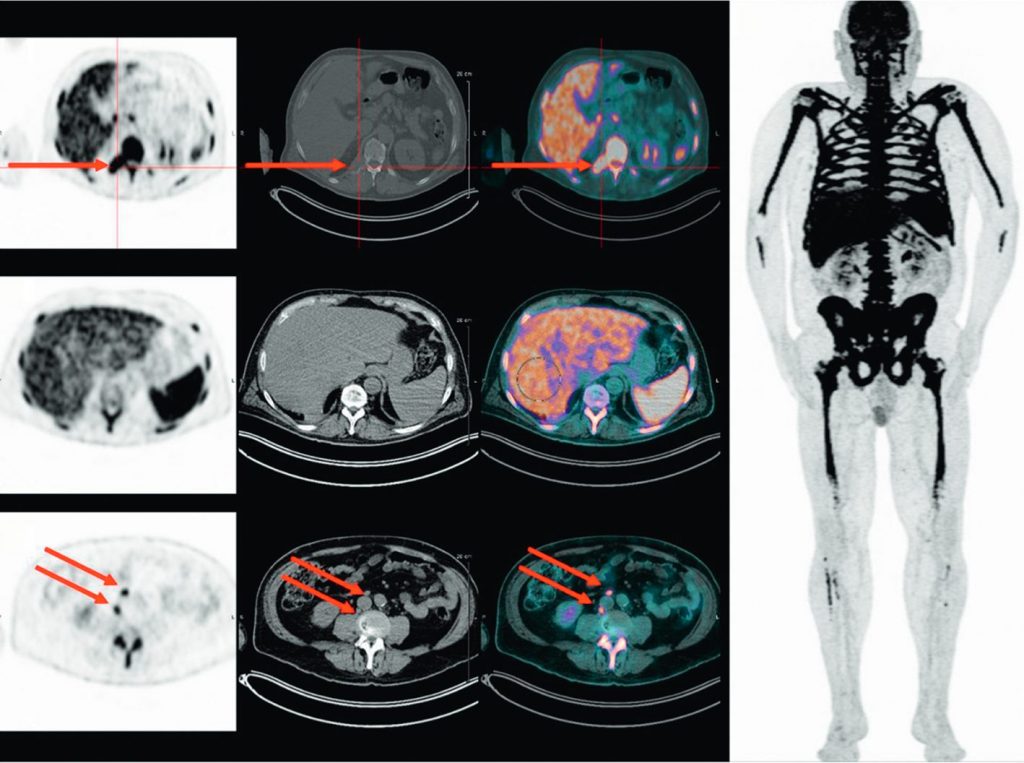

La TEP-TDM au 18FDG est également considérée comme un outil performant pour le bilan initial des patients atteints de plasmocytome ou de myélome multiple, permettant la détection des lésions osseuses et des lésions extraosseuses, qui sont de mauvais pronostic (figure 80.3).

Fig. 80.3 TEP-TDM au 18FDG effectuée dans le cadre du bilan initial d’un myélome multiple.

La TEP-TDM au 18FDG montre une fixation très intense et pathologique du squelette et met en évidence des fixations extraosseuses, notamment lymphatiques et spléniques.

Plusieurs types de lésions peuvent être détectés en TEP-TDM au 18FDG sous forme d’hyperfixations d’intensité variable :

- lésions focales osseuses avec ou sans ostéolyse en regard ;

- atteinte ostéomédullaire diffuse ;

- lésions paramédullaires ;

- lésions extramédullaires.